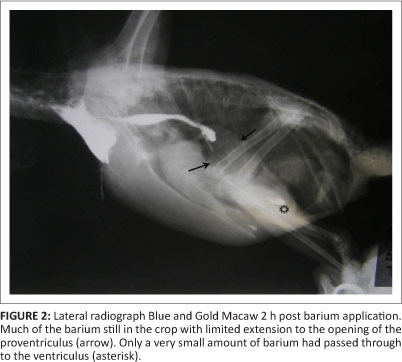

Bird 3, a 2-month-old blue and gold macaw from a different fancier, was examined in March 2011. This parrot had originated from the same breeding facility as birds 1 and 2. This particular bird presented with apparent ventricular obstruction. Radiographic studies revealed distortion of the shape of the cardiohepatic waist, and barium studies indicated very slow passage through to the ventriculus, with much of the barium remaining in the crop and eventually being regurgitated (Figures 1 and 2). A ventriculotomy was performed but no foreign object could be found. Despite supportive and antimicrobial therapy, the bird died two days later. A post-mortem examination was performed by the referring veterinarian and he described emaciation, haemorrhagic enteritis, nephrosis and pneumonia.